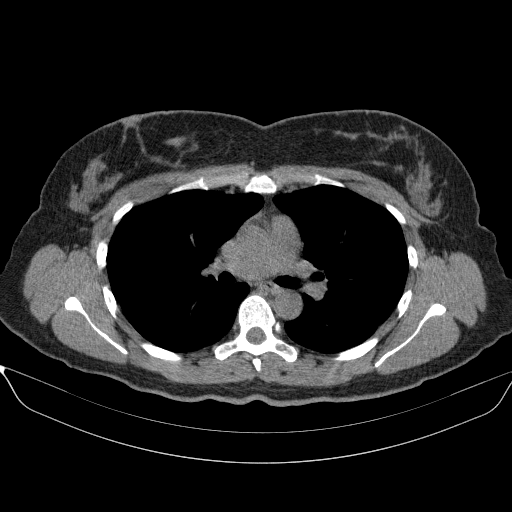

Original VENOUS CT scan

No window - Raw intensity values

Lung window (WL -600, WW 1500 β†’ Low βˆ’1350, High +150)

Mediastinum window (WL 40, WW 400 β†’ Low βˆ’160, High +240)